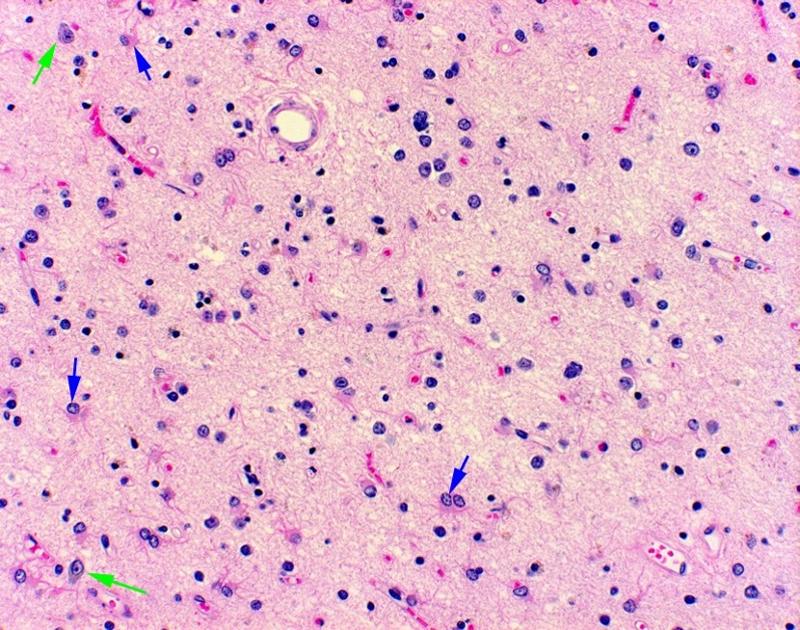

Микрофотографии гистологии глиобластомы головного мозга